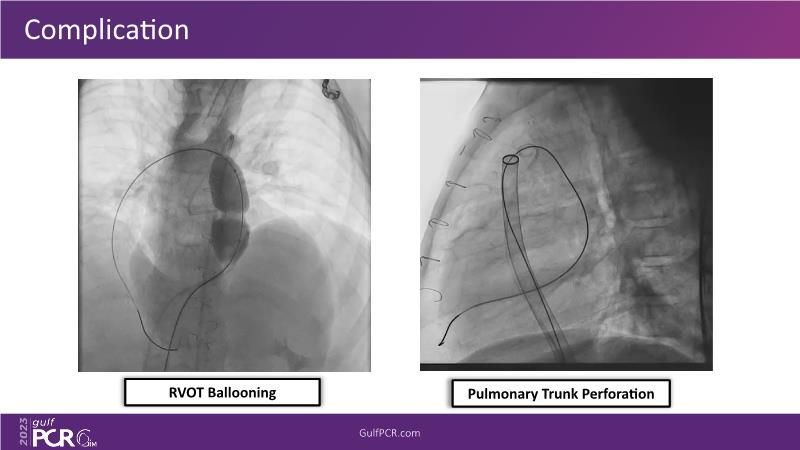

This session is a valuable resource for grasping innovative strategies in handling bifurcation and extended diffuse lesions through dedicated stenting solutions. Explore insights into the advanced Myval next-generation THV technology, unveiling its distinctive features, procedural advantages, and clinical outcomes across a diverse patient pool. Gain understanding into the CorAlign technique, ensuring accurate commissural and coronary alignment while maintaining coronary access. Additionally, delve into the techniques for precise sizing, positioning, and deploying of Myval THV.

- To understand the technique of precise sizing, positioning and deployment of Myval THV